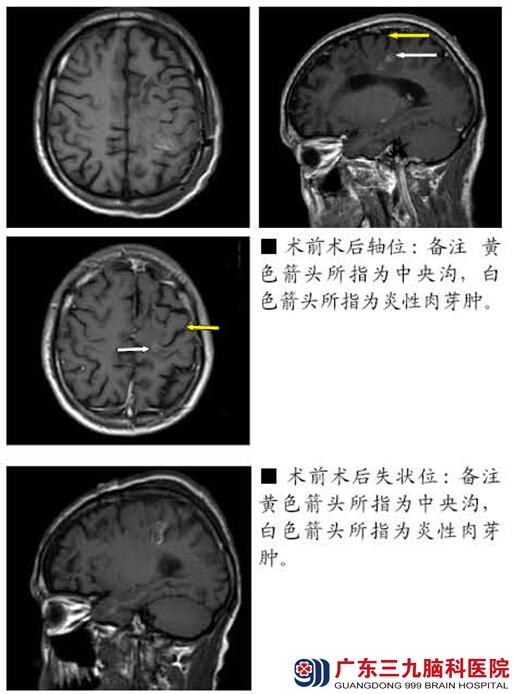

患者吴某,男,46岁,因“发作性意识不清伴肢体抽搐3年余,右侧肢体活动不灵活1年余”于2014年5月份入院。

患者3年余前无明显诱因出现发作性意识不清,发呆状,呼之不应,继之四肢抽搐(具体不详),持续2-3分钟缓解,发作前无先兆表现,以后反复发作,起病2个月内发作3次,2012年发作两次,2013年至今未再出现大发作。去年2月份开始出现右上肢活动不灵活,右手指活动不灵活明显,偶伴右上肢发凉感,但可完成日常基本活动,今年1月份开始觉右下肢乏力伴活动不灵活,逐步加重至行走跛行。为进一步诊治,患者来我院。查体:生命体征平稳,神清,构音稍欠情,语速可,双瞳孔等大正圆,约2.5mm,直接间接对光反射灵敏,双侧眼球各方向活动自如,左侧鼻唇沟较右侧稍浅,伸舌向右侧歪斜,口角向右侧歪斜,右上肢肌力4+级,肌张力稍高,右下肢肌力4-级,肌张力稍低,左侧肢体肌力肌张力正常,右侧肱二头肌腱反射、肱三头肌腱反射、膝腱反射、跟腱反射较对侧活跃,右侧踝阵挛阳性。感觉系统检查未见异常,双侧Hoffmann征(-),右侧Babinski征阳性。颈软,Kernig征、Brudzinski征(-)。右侧轮替试验、指鼻试验笨挫,跟膝胫试验完成好,Romberg征(-)。既往史及个人史:无异常。辅助检查:裂头蚴抗体IgG阳性,头颅MR提示左侧额、顶叶多发异常信号,结合外院核磁共振及实验室检查考虑脑裂头蚴病。入院诊断:1.症状性癫痫(部分性发作,部分继发全面性强直阵挛发作);2.左额中央区病变:裂头蚴可能性大。于2014-06-05在术中唤醒及导航下行左侧额中央区裂头蚴切除术,术中取出裂头蚴活虫一条。术后患者右侧肢体肌力一过性降低至1级,经积极脱水营养神经及康复治疗半月,现肢体肌力已恢复至4级,余情况同术前。